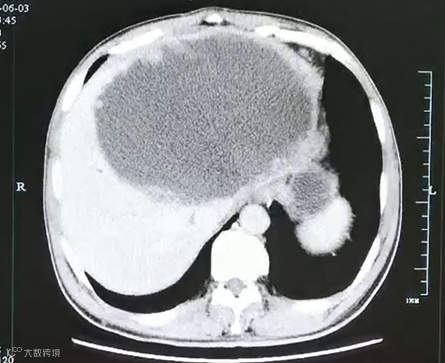

谢师傅的CT结果 杭州市一医院供图

入院后腹部CT检查发现肝脓肿壁上长了很多肿瘤样的结构,而且壁很厚。看来这个肝脓肿不简单。

经过三周的引流和保守治疗,复查增强CT发现谢师傅左肝的脓肿小了一大半,但是肝脓肿厚壁及厚壁上的很多肿瘤样组织没有变化,引流管里引流出来的液体开始减少,而且脓腔也不再进一步缩小,显示出这个脓肿很难自愈。经过肝胆外科、感染科、影像科等多学科会诊及讨论后,医生果断地为患者进行了手术将左半肝切除,完整地拿掉了这个迷雾重重的病灶。